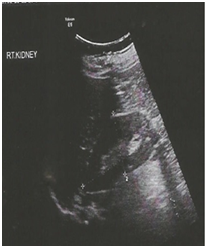

Audiological evaluation (Figure 3A & B) confirmed moderately severe mixed hearing loss on both sides. Ultrasound abdomen and KUB showed few cysts in both kidneys with largest measuring 1.7 x 1 cm in the lower pole of the right kidney (Figure 3A). Renal function tests (RFT) were normal (urea: 20, creatinine: 0.9).

Figure 3A & B Audiological evaluation confirmed moderately severe mixed hearing loss on both sides.